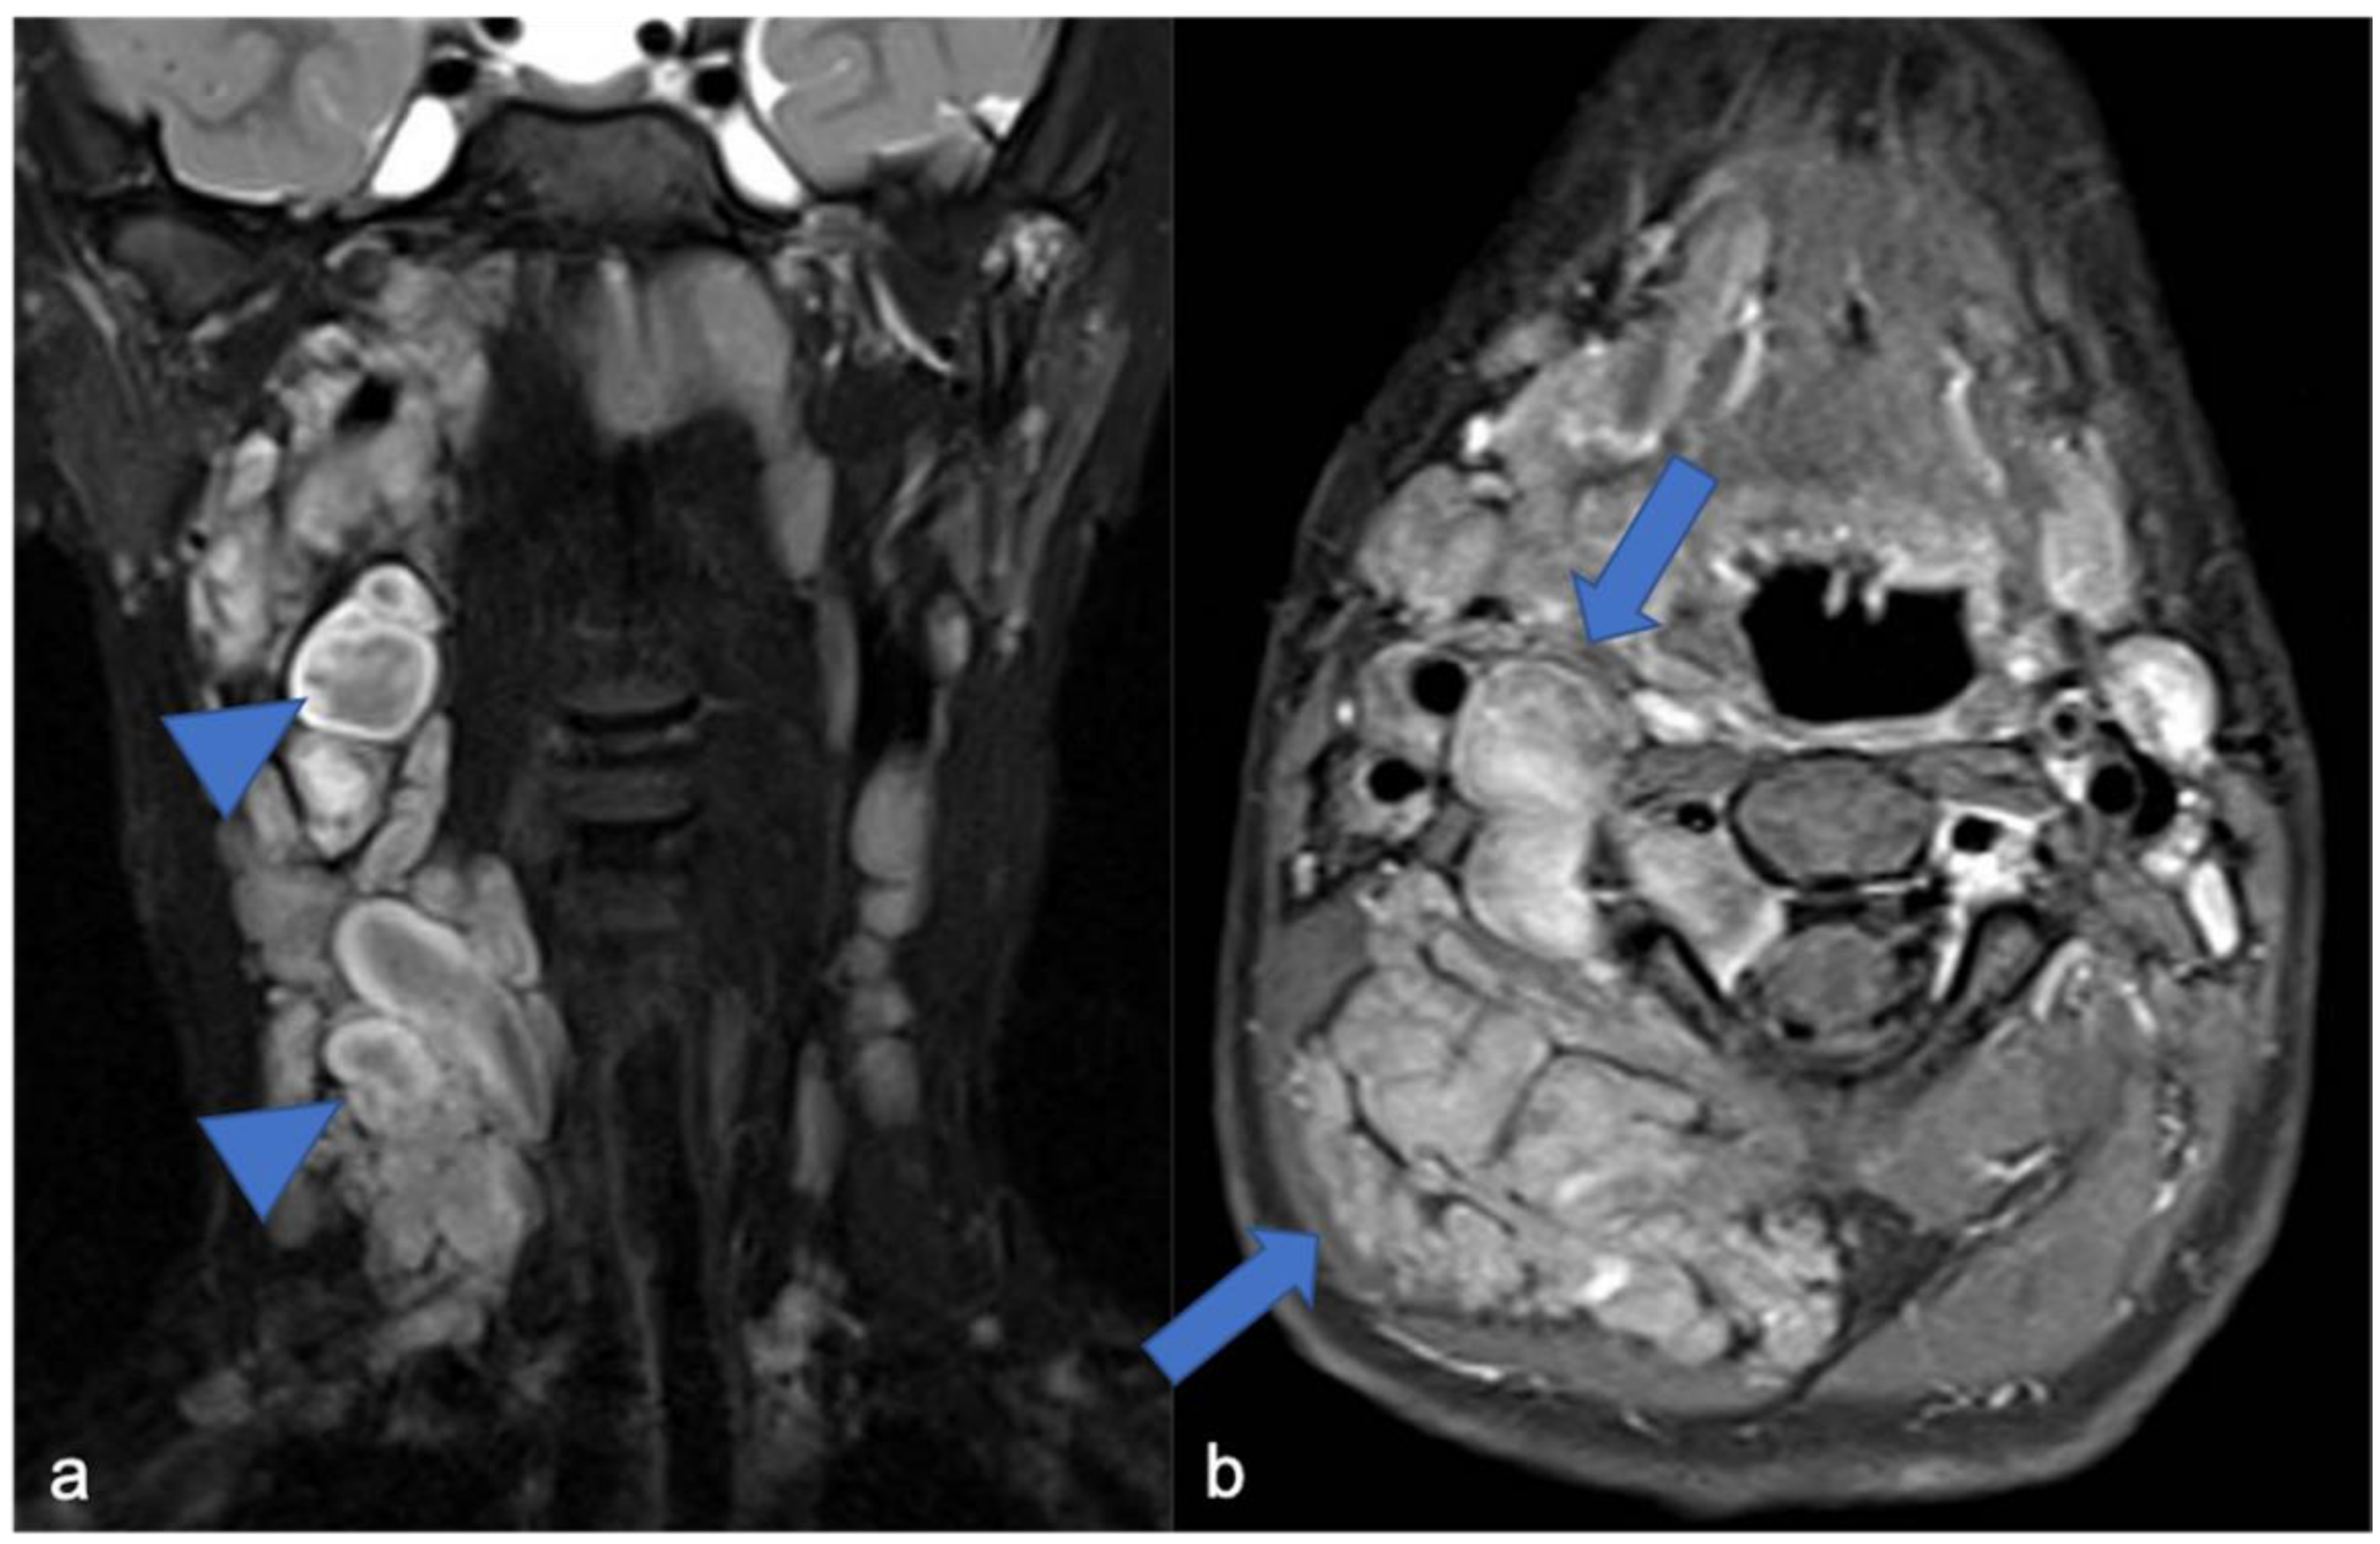

4. Mesenchymal, Non-Meningothelial Tumors

5. Meningiomas and Tumors of the Paraspinal Nerves